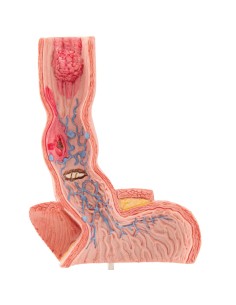

Dal cranio in 22 parti con incastri magnetici ai modelli di colonna vertebrale, da quelli di articolazioni a quelli di cuore, ogni pezzo della nostra collezione è progettato per un’immersione totale nello studio dell’anatomia umana. I nostri modelli, realizzati tramite scansioni di ossa vere, garantiscono un’esperienza tattile autentica e una fedeltà di peso quasi identica agli originali.

Essenziali per studenti e professionisti, i nostri modelli anatomici sono strumenti didattici che permettono di osservare le strutture anatomiche con precisione, eliminando la necessità di dissezioni o studi invasivi. Sono inoltre utili per spiegare ai pazienti le patologie, rendendo la comunicazione più efficace e risparmiando tempo prezioso.